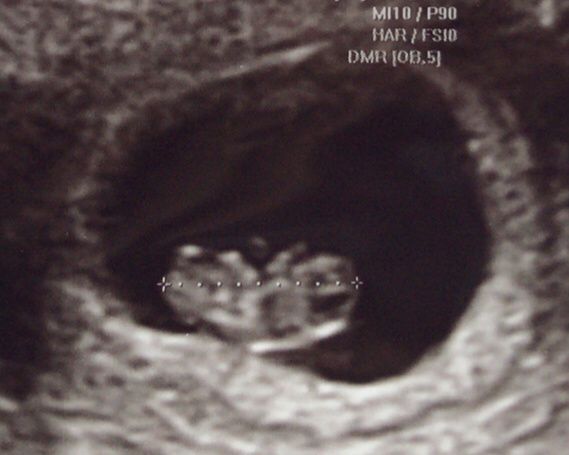

Metodo ramzi

Da Melania , Il 24 Settembre 2019 alle 14:23

Ciao sono nuova in questa comunity so del metodo ramzi chi mi puo aiutare a capire? Ecco una ecografia di 8 settimane interna.